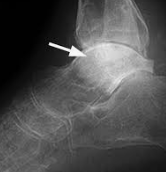

支持プレートは、海綿質の多い骨領域、主として骨幹端に使用されるもので、薄い皮質を支えて、骨片の動きを防ぐはたらきをします。